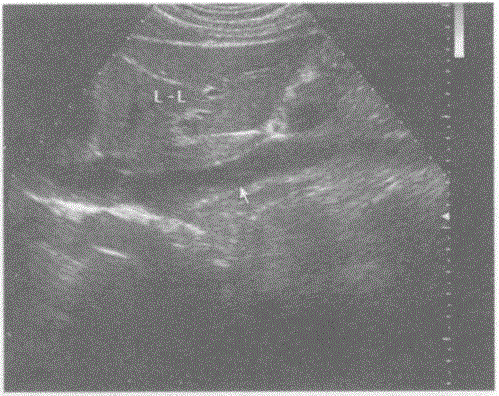

问题 请回答下图箭头所指部位及彩图取样门宽所采及部位的解剖名称:

选项 A.门静脉 B.下腔静脉 C.腹主动脉 D.肝静脉

答案 B